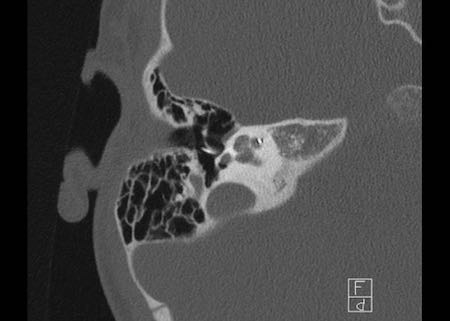

Bên trái là hình ảnh của một bé gái 2 tuổi.

Các hình ảnh từ kết quả chụp CT được thực hiện trước khi cấy ốc tai điện tử.

Quan sát thấy dị dạng nhẹ ở đỉnh ốc tai – không có sự phân tách giữa vòng thứ hai và vòng thứ ba, và trụ ốc tai xương vắng mặt.

Cống tiền đình bình thường.